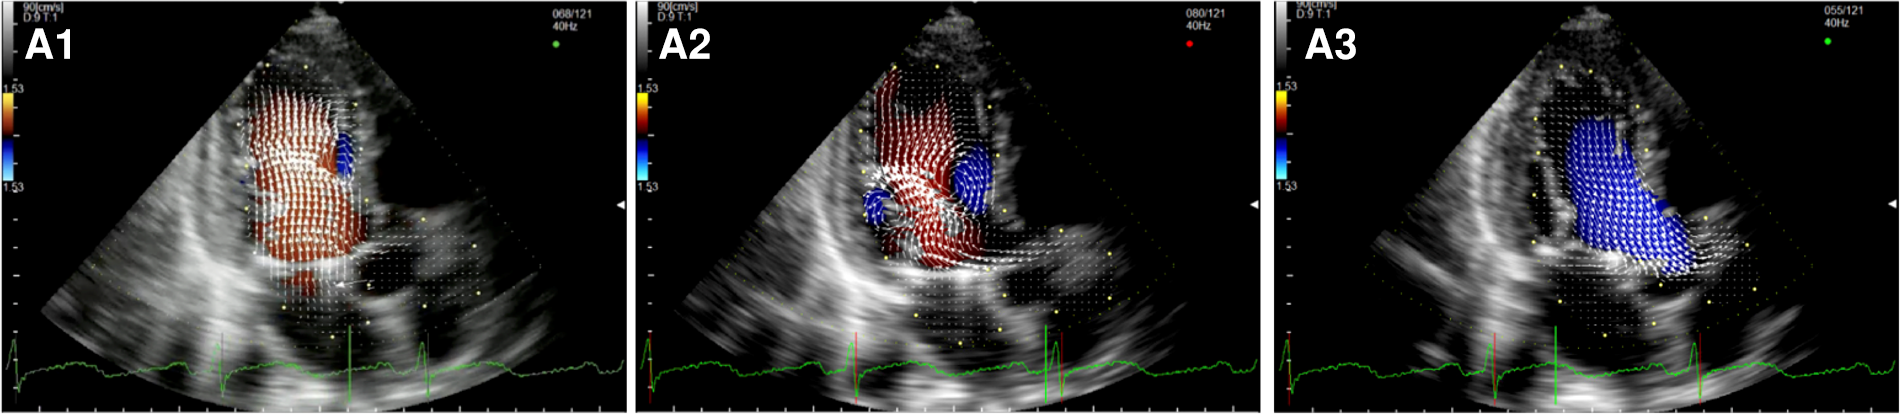

After MVR with bioprostehsis (Figure 3, panel A1,A2,A3, Supplementary Video S5), we can observe in diastole only one vortex distal to the bioprosthetic valve with a counterclockwise rotation (opposite to the healthy control). The vortex occupies the center of the LV cavity to redirect blood toward the LVOT. In systole, we observed intraventricular vortices probably related to the LV systolic dysfunction. Moreover, it is possible to notice a vortex rotating clockwise within the struts of the bioprosthesis. Similarly, in patients with a mechanical prosthesis in antianatomical orientation (Figure 3, panel B1,B2,B3, Supplementary Video S6), during diastole, there is a major counterclockwise vortex in the LV mid cavity and a smaller clockwise one that disappears quickly. The main vortex redirects the flow towards the LVOT. In this group, turbulence during systole is less evident.

Figure 3

Apical long-axis view. Intracardiac flow vectors in early diastole (A1,B1) and late diastole (A2,B2) after mitral valve replacement with bioprosthesis and mechanical prosthesis (antianatomicalorientation) respectively; intracardiac flow vectors in mid-systole (A3,B3) after mitral valve replacement with bioprosthesis and mechanical prosthesis (antianatomicalorientation) respectively.